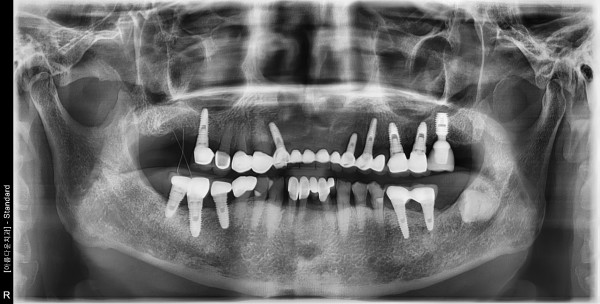

70대 남성 임플란트 식립